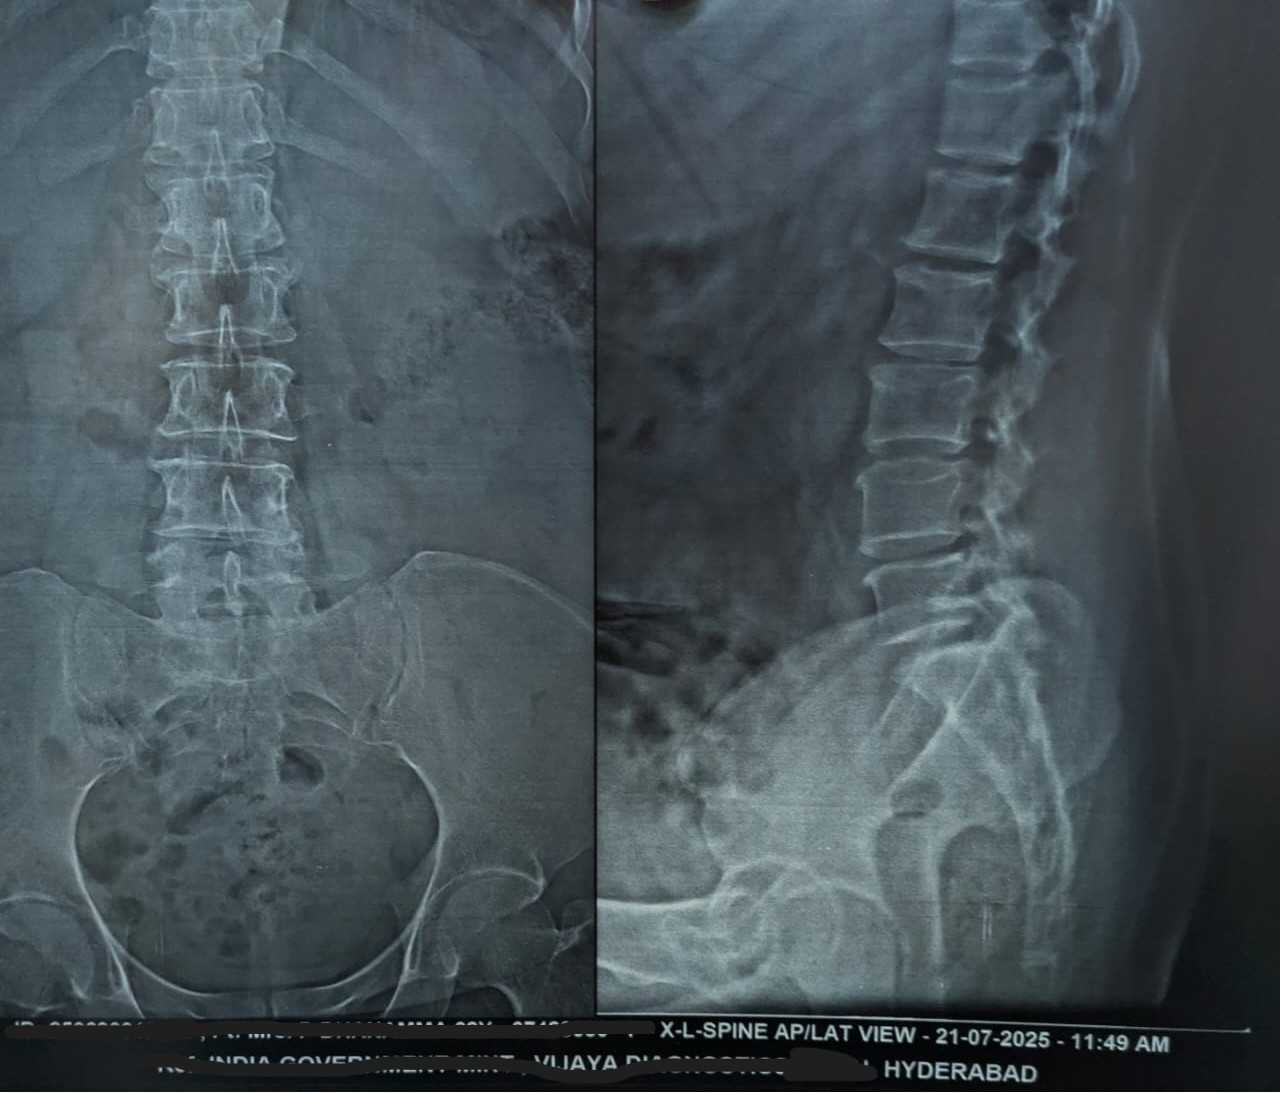

• X-ray (Before): Cervical and lumbar spondylotic changes with mild disc-space reduction.

Lumbar spine X-ray before Marma therapy (28 Jun 2025)

Before — 28 Jun 2025